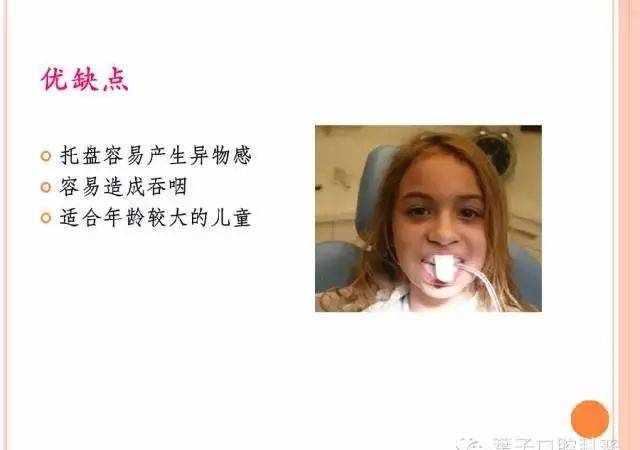

(1)氟凝胶

(2)氟化泡沫

(3)氟保护漆